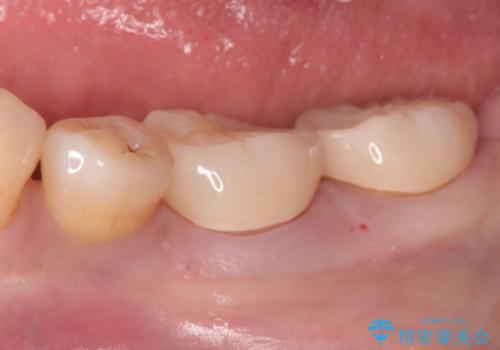

- 以前治療したところがしみて、アイスが食べられないから被せものの治療をしてほしいと来院された患者様です。

咬合が強く、歯牙にマイクロクラックが入っている状態でした。歯髄は保存可能と診断され、フルジルコニアクラウンによる治療を行いました。

咬合面に広範囲の修復物がある状態で中心に強い力が加わると歯牙は外方性の歪みが生じ、マイクロクラックができます。これを防ぐには、咬頭被覆するアンレー、もしくはクラウンによる治療が必要です。